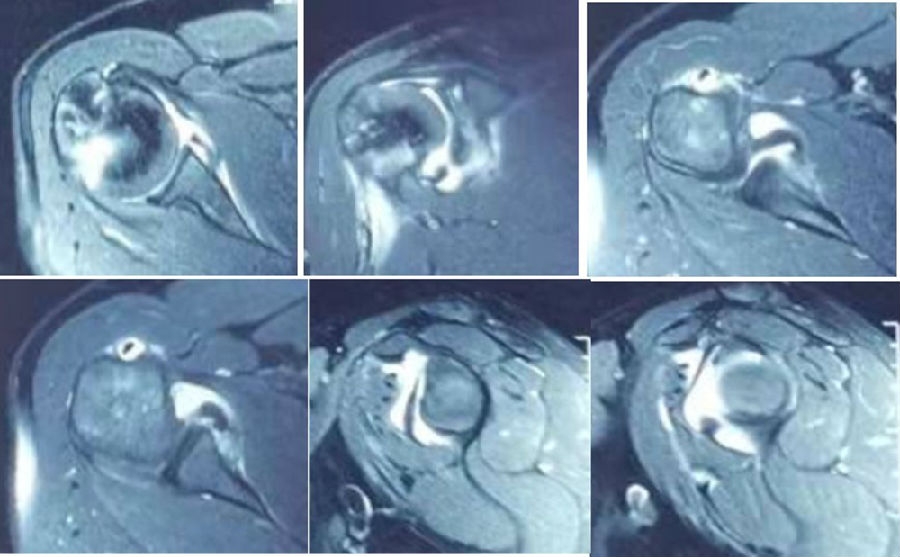

图39 此次复发脱位MR评估

图40 影像学评估

双侧CT三维扫描显示:D=34mm,d=3mm,d/D=肩胛盂骨缺损9%;GT=25.2mm,HIS=30mm。

该患者为轨迹外Hill-Sachs损伤,需要做bankart修补,同时轨迹外做remplissage手术。

图44 术前MRI

图45 CT D=26mm d=8mm(上患侧,下健侧)

图46 CT d/D=30.7% GT=0.83D-d=13.6mm Hill-Sachs损伤I级,骨缺损 >25%